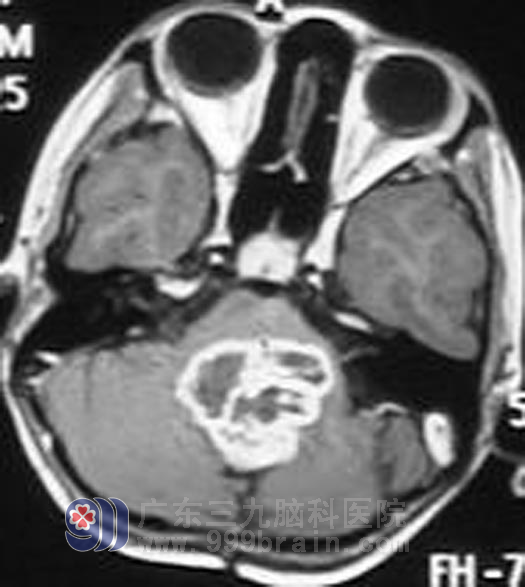

复发时

到了2007年9月,小莹莹已经6岁了,正是幼儿园毕业准备上小学的时候,莹莹再次出现恶心呕吐,警觉的父母直接带这莹莹来到了广东三九脑科医院肿瘤综合治疗中心,查头部MR显示四脑室见明显强化灶,蔡林波主任检查此时的小莹莹除了恶心呕吐症状以外还出现了一系列的阳性体征,包括反应迟钝,双眼水平眼震,双眼外展。出现右脚跛行,这一次的肿瘤似乎比第一次来得更加凶猛。蔡林波主任结合莹莹的病史考虑小莹莹肿瘤复发可能性大,建议再次手术,术后再行放疗。父母考虑到小莹莹身体瘦小,且之前已经经历过一次手术,担心手术风险太大,遂决定不再考虑手术治疗,要求直接放疗。通过完善的检查,指定个性的治疗方案。2008年10月小莹莹接受了头部的适行调强放疗,距离第一次发病治疗正好两年。放疗结束后小莹莹恶心呕吐症状已经完全消失,复查头颅MR肿瘤较前缩小。http://www.999brain.com/